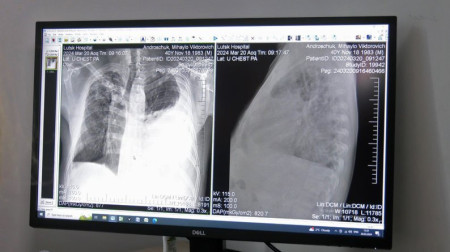

Щодня у рентген-кабінеті центру проходять обстеження орієнтовно 60 людей. Як зазначила завідувачка відділення Валентина Мостова, сюди направляють пацієнтів із підозрою на туберкульоз.

«Це туберкульоз в легенях і великий плеврит лівобічний ексудативний плеврит, тобто, набирається рідина в плевральній порожнині. Він до нас поступає на лікування, лікується і виписується майже здоровим», – сказала лікарка.